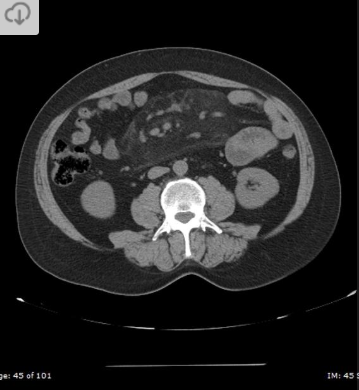

Fibrilação atrial; Dor lombar

Infarto renal.

Opacidade triangular em cunha; realce cortical periférico.